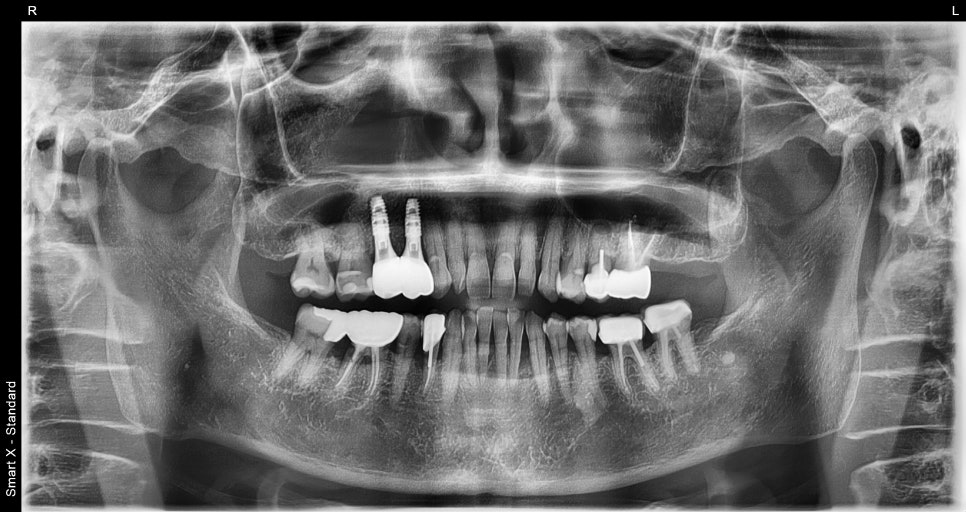

임플란트 전 검사

: 왜 CT·파노라마가 꼭 필요할까?

임플란트는 정확한 진단에서 시작됩니다.

서울오브치과병원에서는 파노라마 촬영과

CT 촬영을 통해 다음을 확인합니다.

잇몸뼈의 두께와 높이

신경의 위치

기존 염증 여부

주변 치아 상태

60대 환자분 역시 이 검사를 통해

“임플란트를 심기 전에 뼈를 보강해야 한다”는

결론을 얻었습니다.

Previous image Next image

이는 환자마다 뼈의 양 · 구조 · 잇몸 상태가

다르기 때문입니다.

③ 임플란트 식립(나사 심기)

위 사례에서도 두 개의 어금니 위치에

임플란트를 심는 수술이 안정적으로 마무리되었습니다.